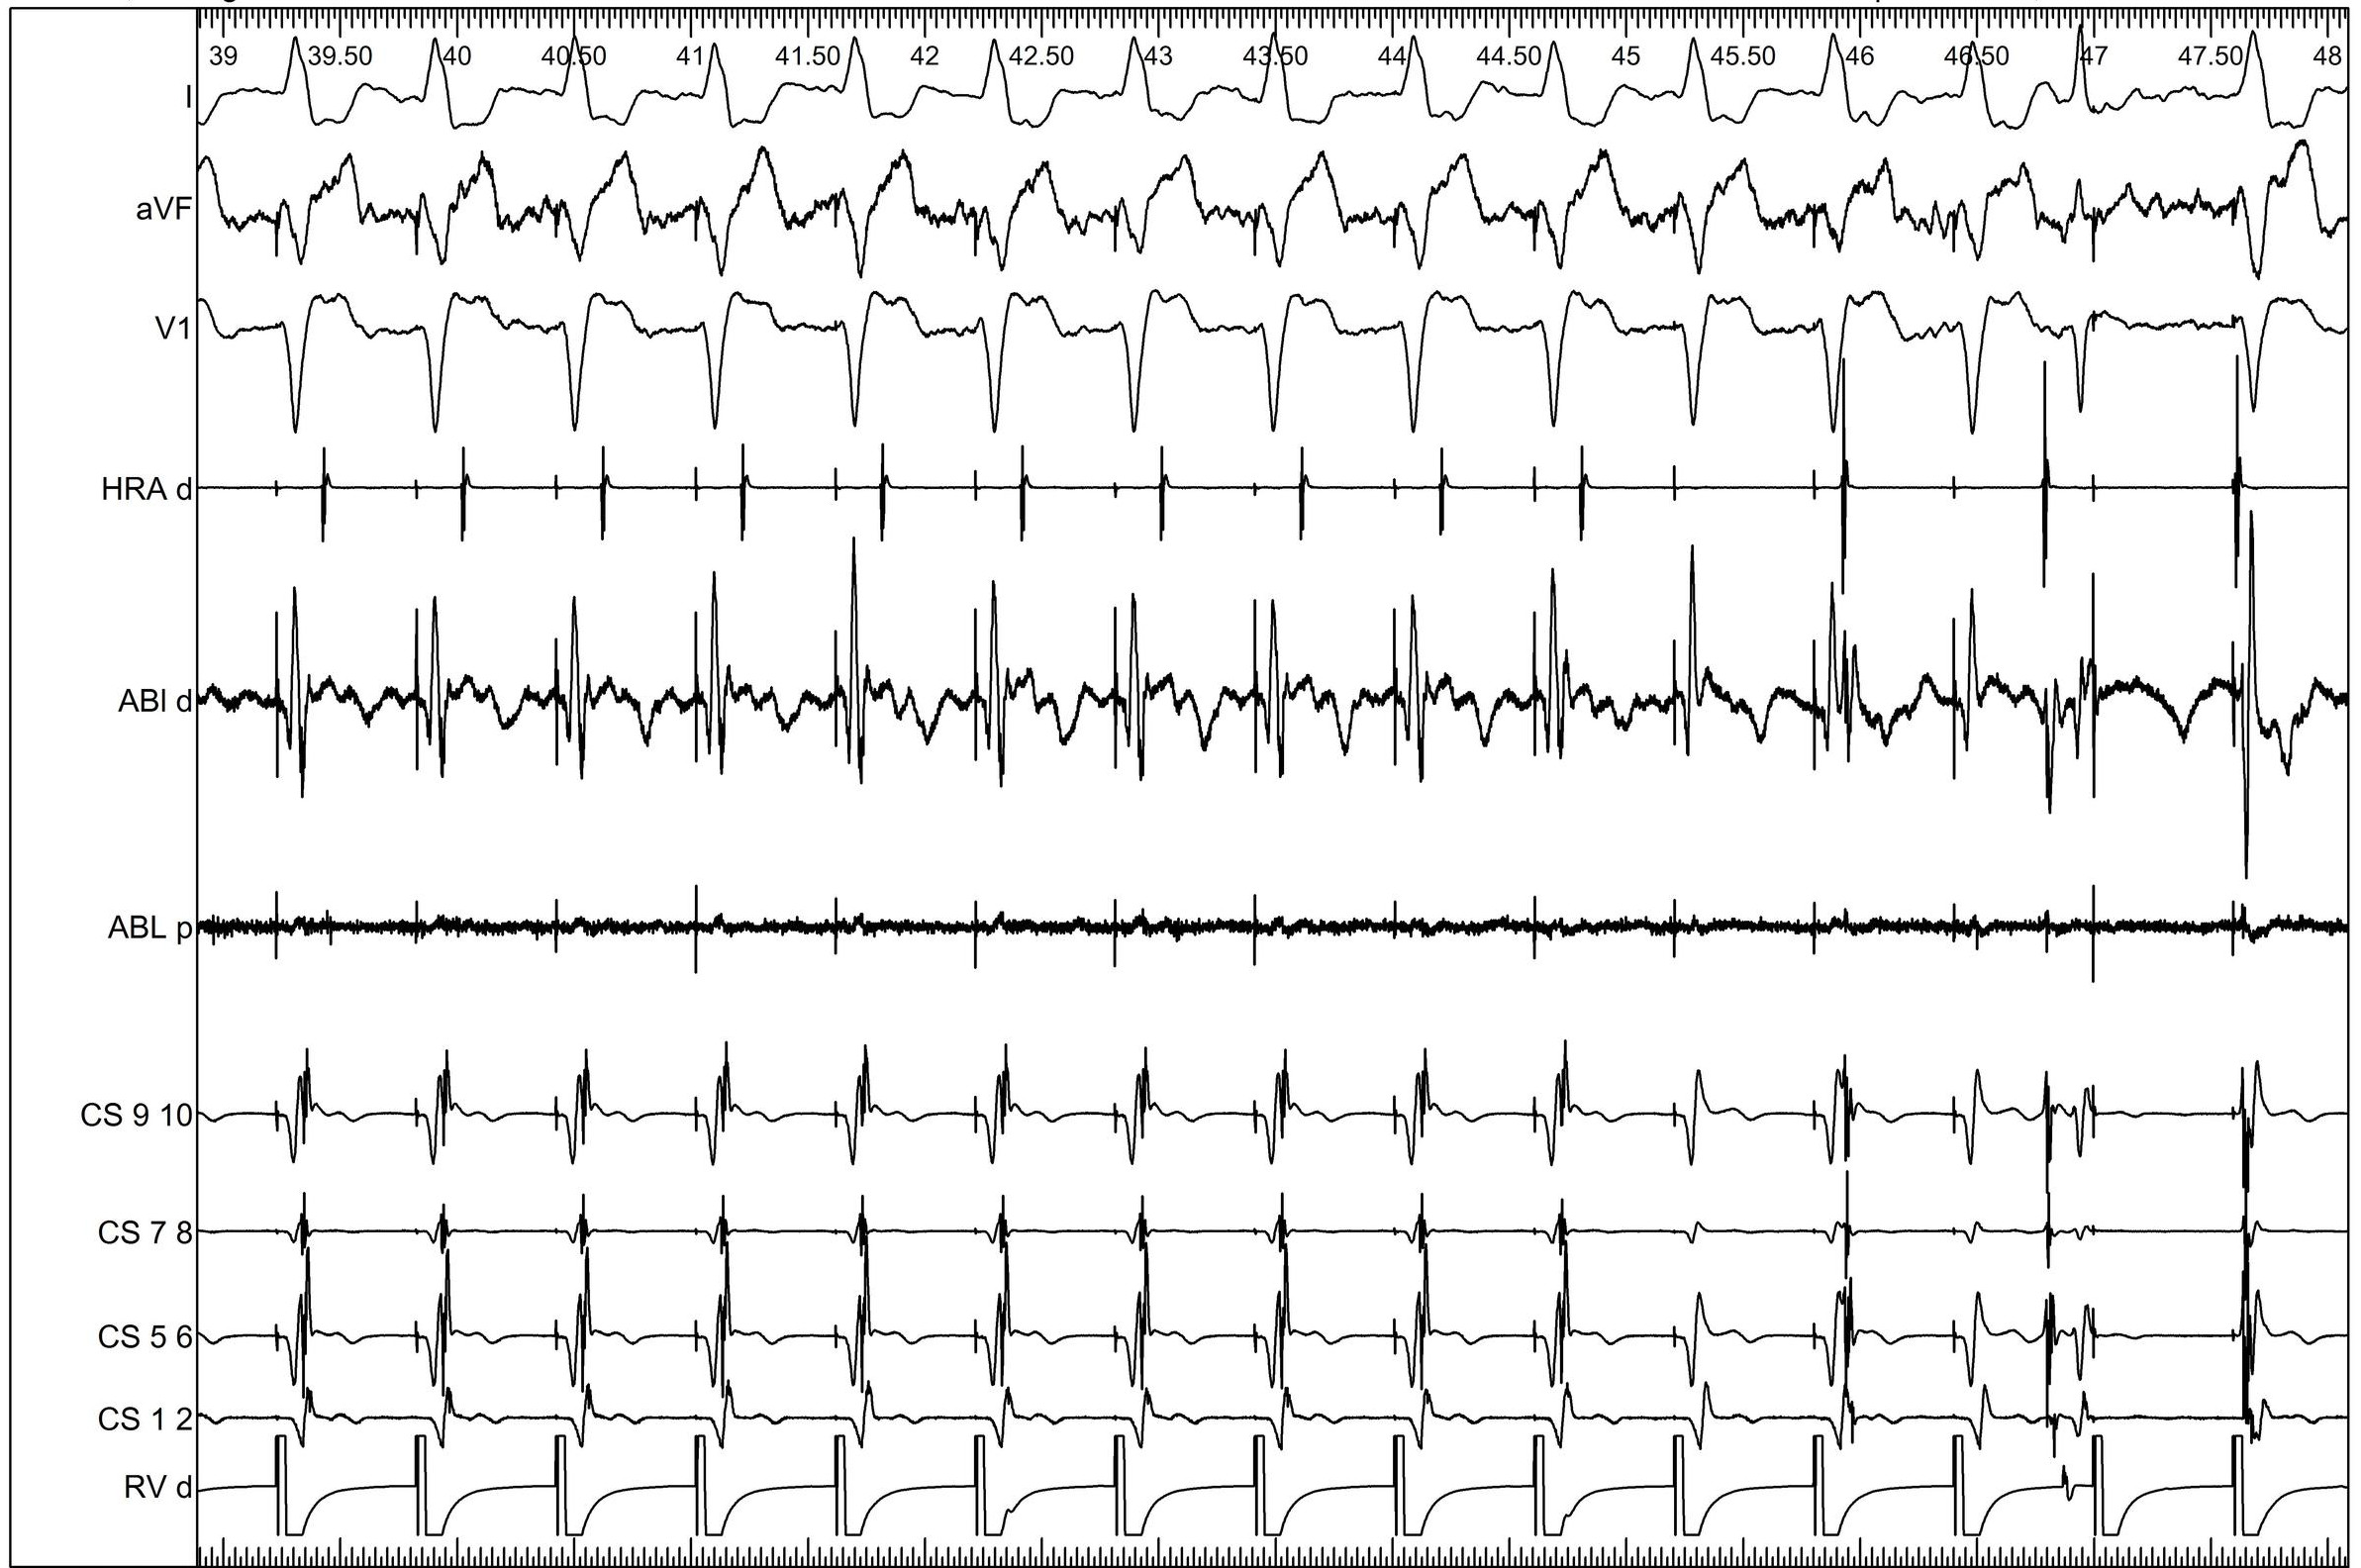

Parahisian

08_parahisian.jpg

Parahisian pacing in a Posteroseptal AP

php.png

Measurement of the ventriculoatrial interval from the coronary sinus during para-Hisian pacing may fail to distinguish ventriculoatrial nodal conduction from conduction over a septal accessory pathway. Iijima, Takafumi et al. Journal of Arrhythmia , Volume 31 , Issue 1 , 33 - 37